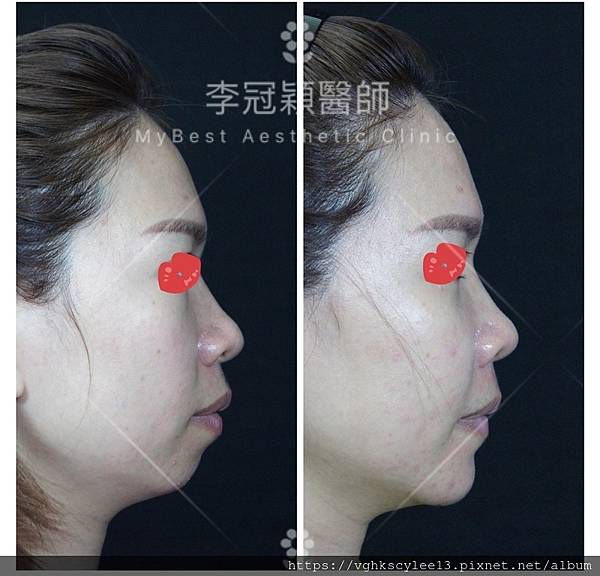

下圖案例:下巴整形打造V型臉的效果(客製化goretex複合式假體)

下圖:後縮小下巴會堆積雙下巴和嘴邊肉皮膚,視覺老態。經過客製化3D導航下巴改善外觀老態,提升年輕化。

過短後縮下巴,因組織支撐力弱而容易有雙下巴(上圖),嘴邊肉(下圖)以及下顎腺不明顯,整體而言除了失衡還有點流失下垂的『老態』。

案例:下巴整形(客製化goetex下巴假體)

下圖: 3D客製化精準墊下巴(goretex)

案例分享:3D列印導航客製化goretex下巴